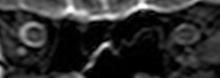

The third case of visual changes while on board the ISS had no changes in visual acuity and no complaints of headaches, transient visual obscurations, diplopia or pulsatile tinnitus during the mission. Upon return to Earth, no eye issues were reported by the astronaut at landing. Fundus examination revealed bilateral, asymmetrical disc edema. There was no evidence of choroidal folds or cotton-wool spots, but a small hemorrhage was observed below the optic dics in the right eye. This astronaut had the most pronounced optic-disc edema of all astronauts reported to date, but had no choroidal folds, globe flattening or hyperopic shift. At 10 days post landing, an MRI of the brain and eyes was normal, but there appeared to be a mild increase in CSF signal around the right optic nerve.[3]